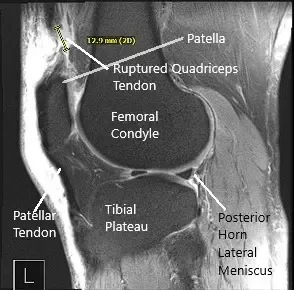

Le diagnosticaron clínicamente una rotura del cuádriceps. Se realizó una resonancia magnética de la rodilla derecha que sugirió una ruptura de grosor total del tendón distal del cuádriceps que ocurrió a 1,8 cm proximal del lugar de inserción rotuliana, lo que resultó en un desgarro de hasta 1,5 cm